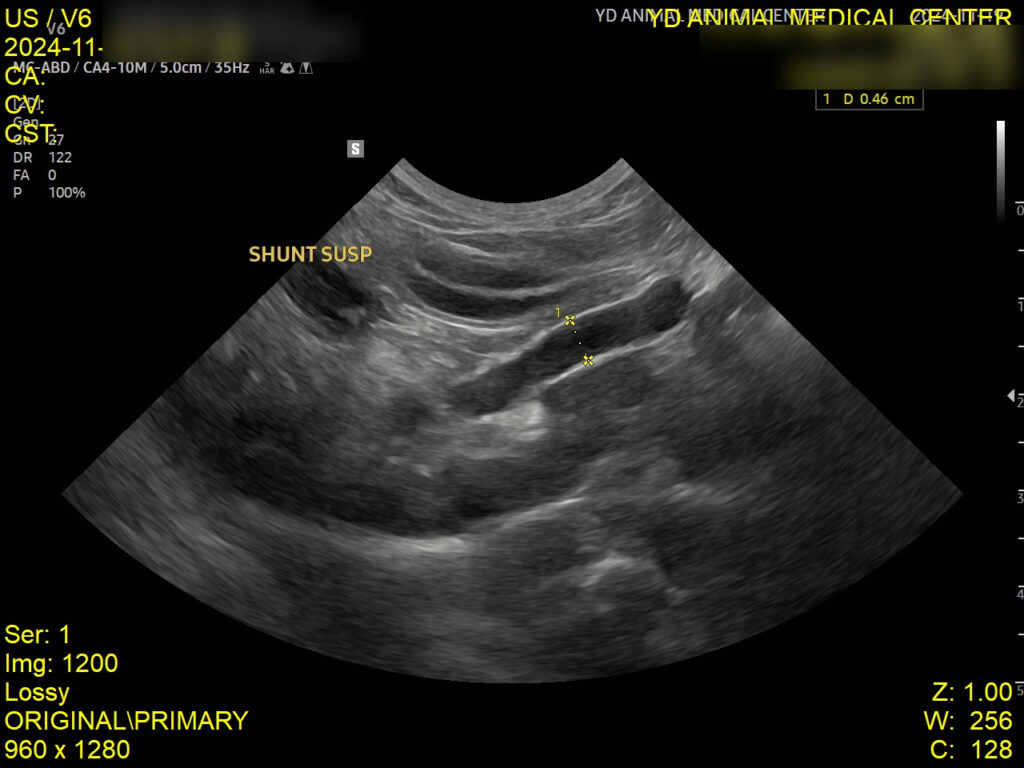

복부 초음파에서는 우측 위위정맥(Rt. gastric vein)에서 비정상 혈관이 관찰되었습니다. 이는 간으로 가는 혈류가 우회 중인 것으로 간문맥전신단락(PSS)가 의심 되었습니다.